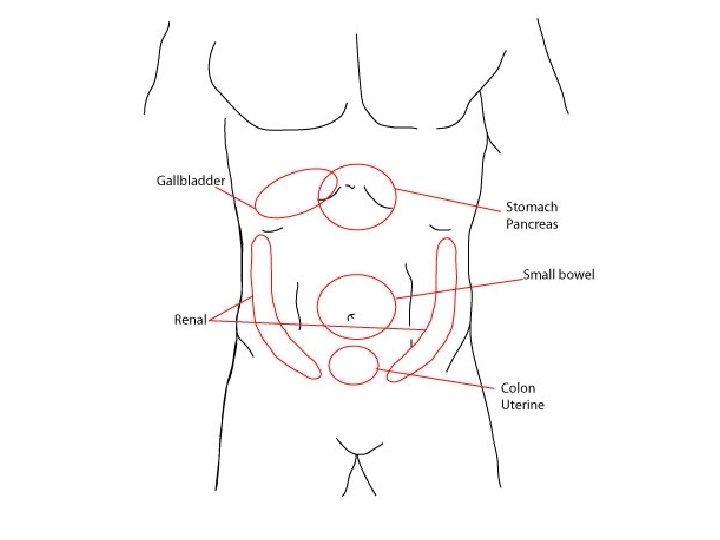

• KLINIKA: - Shenja kryesore eshte dhimbja abdominale e forte qe lokalizohet me veshtiresi nga i semuri. - Dhimbja: fillon ne regionin epigastrik, mund te perhapet edhe ne shpine ose ne shpatullen e djathte, por kryesisht perqendrohet ne kuadrantin superior dexter. - Eshte nje dhimbje me intensitet ne rritje. - Kjo dhimbje pasqyron tensionin dhe inflamacionin e mureve te kolecistes, si pasoje e obstruksionit kalkuloz te duktusit cistik.

• DHIMBJA: Vjen nga nje peristaltike e sforcuar per te kaluar pengesen. Me shpesh paraqitet rreth umbilikusit ne epigaster, per segmentet e siperme te zorreve te holla dhe ne kuadrantet inferior te abdomenit ne okluzionin e segmentit te poshtem te kolonit

KLINIKA: • DHIMBJA: Fillimisht e moderuar ne forme kolike ne regionin periumbilikal, me pas shnderrohet ne dhimbje te qendrueshme e zhvendosur ne kuadrantin inferior dexter.

EKZAMINIMET LABORATORIKE: - Hemogram: Leukocitoze - Ekzaminimi i urines: per diagnoze diferenciale DIAGNOZA DIFERENCIALE: - Kolecistit - Kolika renale dexter - Ulcer gastroduodenale e perforuar - Okluzion intestinal

KOLIKAT RENALE

KUJDES!!!!! • MI- Dhimbje epigastrike • Pneumonia- Dhimbje ne abdomenin e siperm